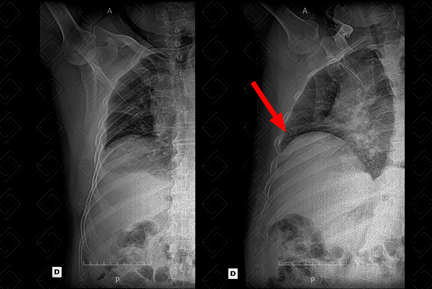

Descrição das figuras: Incidência em AP à esquerda onde fica quase impossível localizar o local da fratura. Já na incidência em oblíquo, à direita da tela, conseguimos observar com clareza o traço de fratura (seta vermelha). Por isso, a importância de realizar a radiografia de arcos costais em oblíquo.

Fratura de arcos costais: Comumente, está associada a mecanismos de trauma. No entanto, na população pediátrica, deve-se estar atento para múltiplas fraturas de arcos costais, especialmente aquelas em fases distintas de consolidação (pensar na possibilidade de maus-tratos). [cms-watermark]

• Radiografia de arcos costais AP e oblíquo: Em cerca de metade dos casos, pode evidenciar com clareza a fratura. No entanto, diante do contexto de trauma, não é exame de escolha;